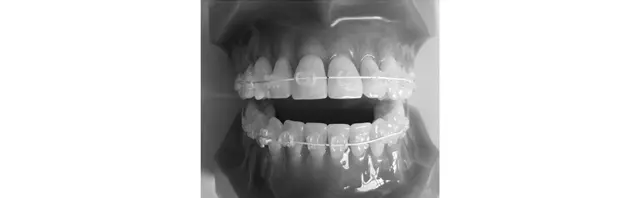

マウスピース矯正

取りはずしができるので食事や歯磨きにストレスなし

固めのマウスピースを長時間装着し歯並びを整える方法。部分にも対応し、矯正後の後戻りの調整にも最適。透明で目立ちにくく、取りはずし可能なので、食事や歯磨きがしやすい。ただし一日の装着時間が短いと矯正期間が延びる。目安は上下で¥480,000〜。